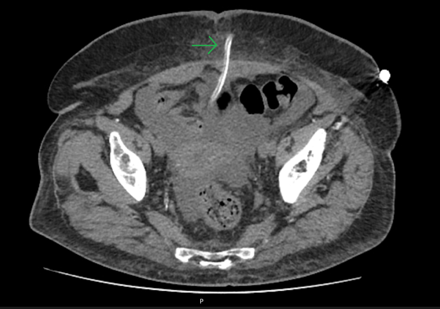

To assess for a possible peri-catheter leak and rule out a catheter fracture, a computed tomography (CT) scan was performed with contrast infusion into the peritoneal cavity (Figure 2 and Figure 3). The protocol included a standard non-contrast CT scan followed by a 2 h dwell of 1.36% glucose dialysate to which 100 ml of contrast was added, comprising a total of 2 liters of infused fluid.

Figure 2. Transversal CT cut

A second CT scan was performed afterward. Imaging showed dialysate drainage through the midline in the periumbilical region, where there was also significant adipose tissue densification. Intraperitoneal pressure was not measured at this time.